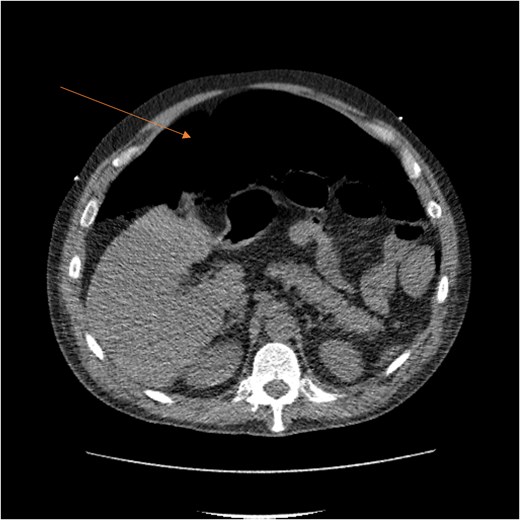

A massive transfusion protocol was initiated, and the patient received four units of packed red blood cells, six units of fresh frozen plasma, two units of platelets, and bicarbonate boluses. A CT abdomen and pelvis was performed to reassess the RSH, revealing an interval enlargement (15.3 × 10.7 × 20.4 cm) with a focal blush at the inferior portion, concerning for active extravasation (Fig. 3). The patient was hemodynamically stabilized and underwent inferior vena cava (IVC) filter placement once his hemoglobin reached 8 g/dl.

CT scan demonstrating pneumo-peritoneum (arrow), indicative of a hollow viscus perforation.